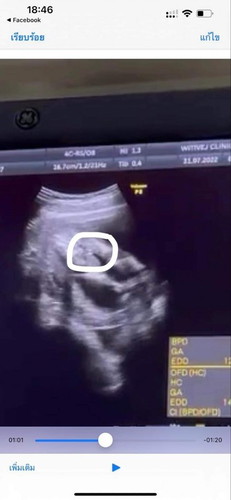

มาทายกัน👶🏻👧🏻แม่ซาวด์มาแล้วแต่หมอยังไม่คอนเฟิม

มาลองเดากันเล่นๆ ให้หัวใจอีแม่ได้ลุ้นตาม เพราะแม่เดาว่าเป็นหญิง ท้องแรก ไม่มีอาการแพ้ท้องเลย แม่ชอบกินแต่เมนูเส้นๆ ชอบแต่งตัวสวยๆ ในซาวด์ ดุ๊กดุ๋ย 16 week ค่ะ#ขอบคุณสำหรับคำตอบค่ะ